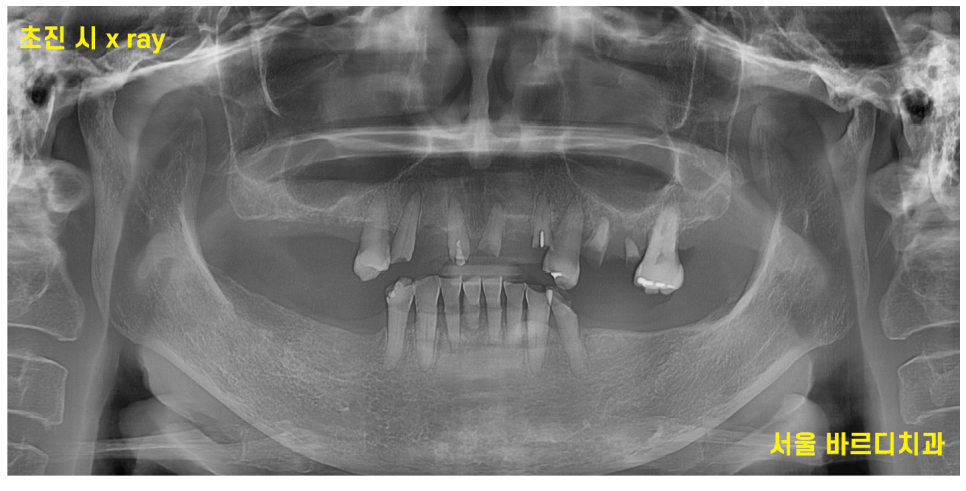

초진 내원 시 찍은 파노라마 사진입니다.

한눈에보기에도 치아가 부러지고

몇개 안남아 있죠~?